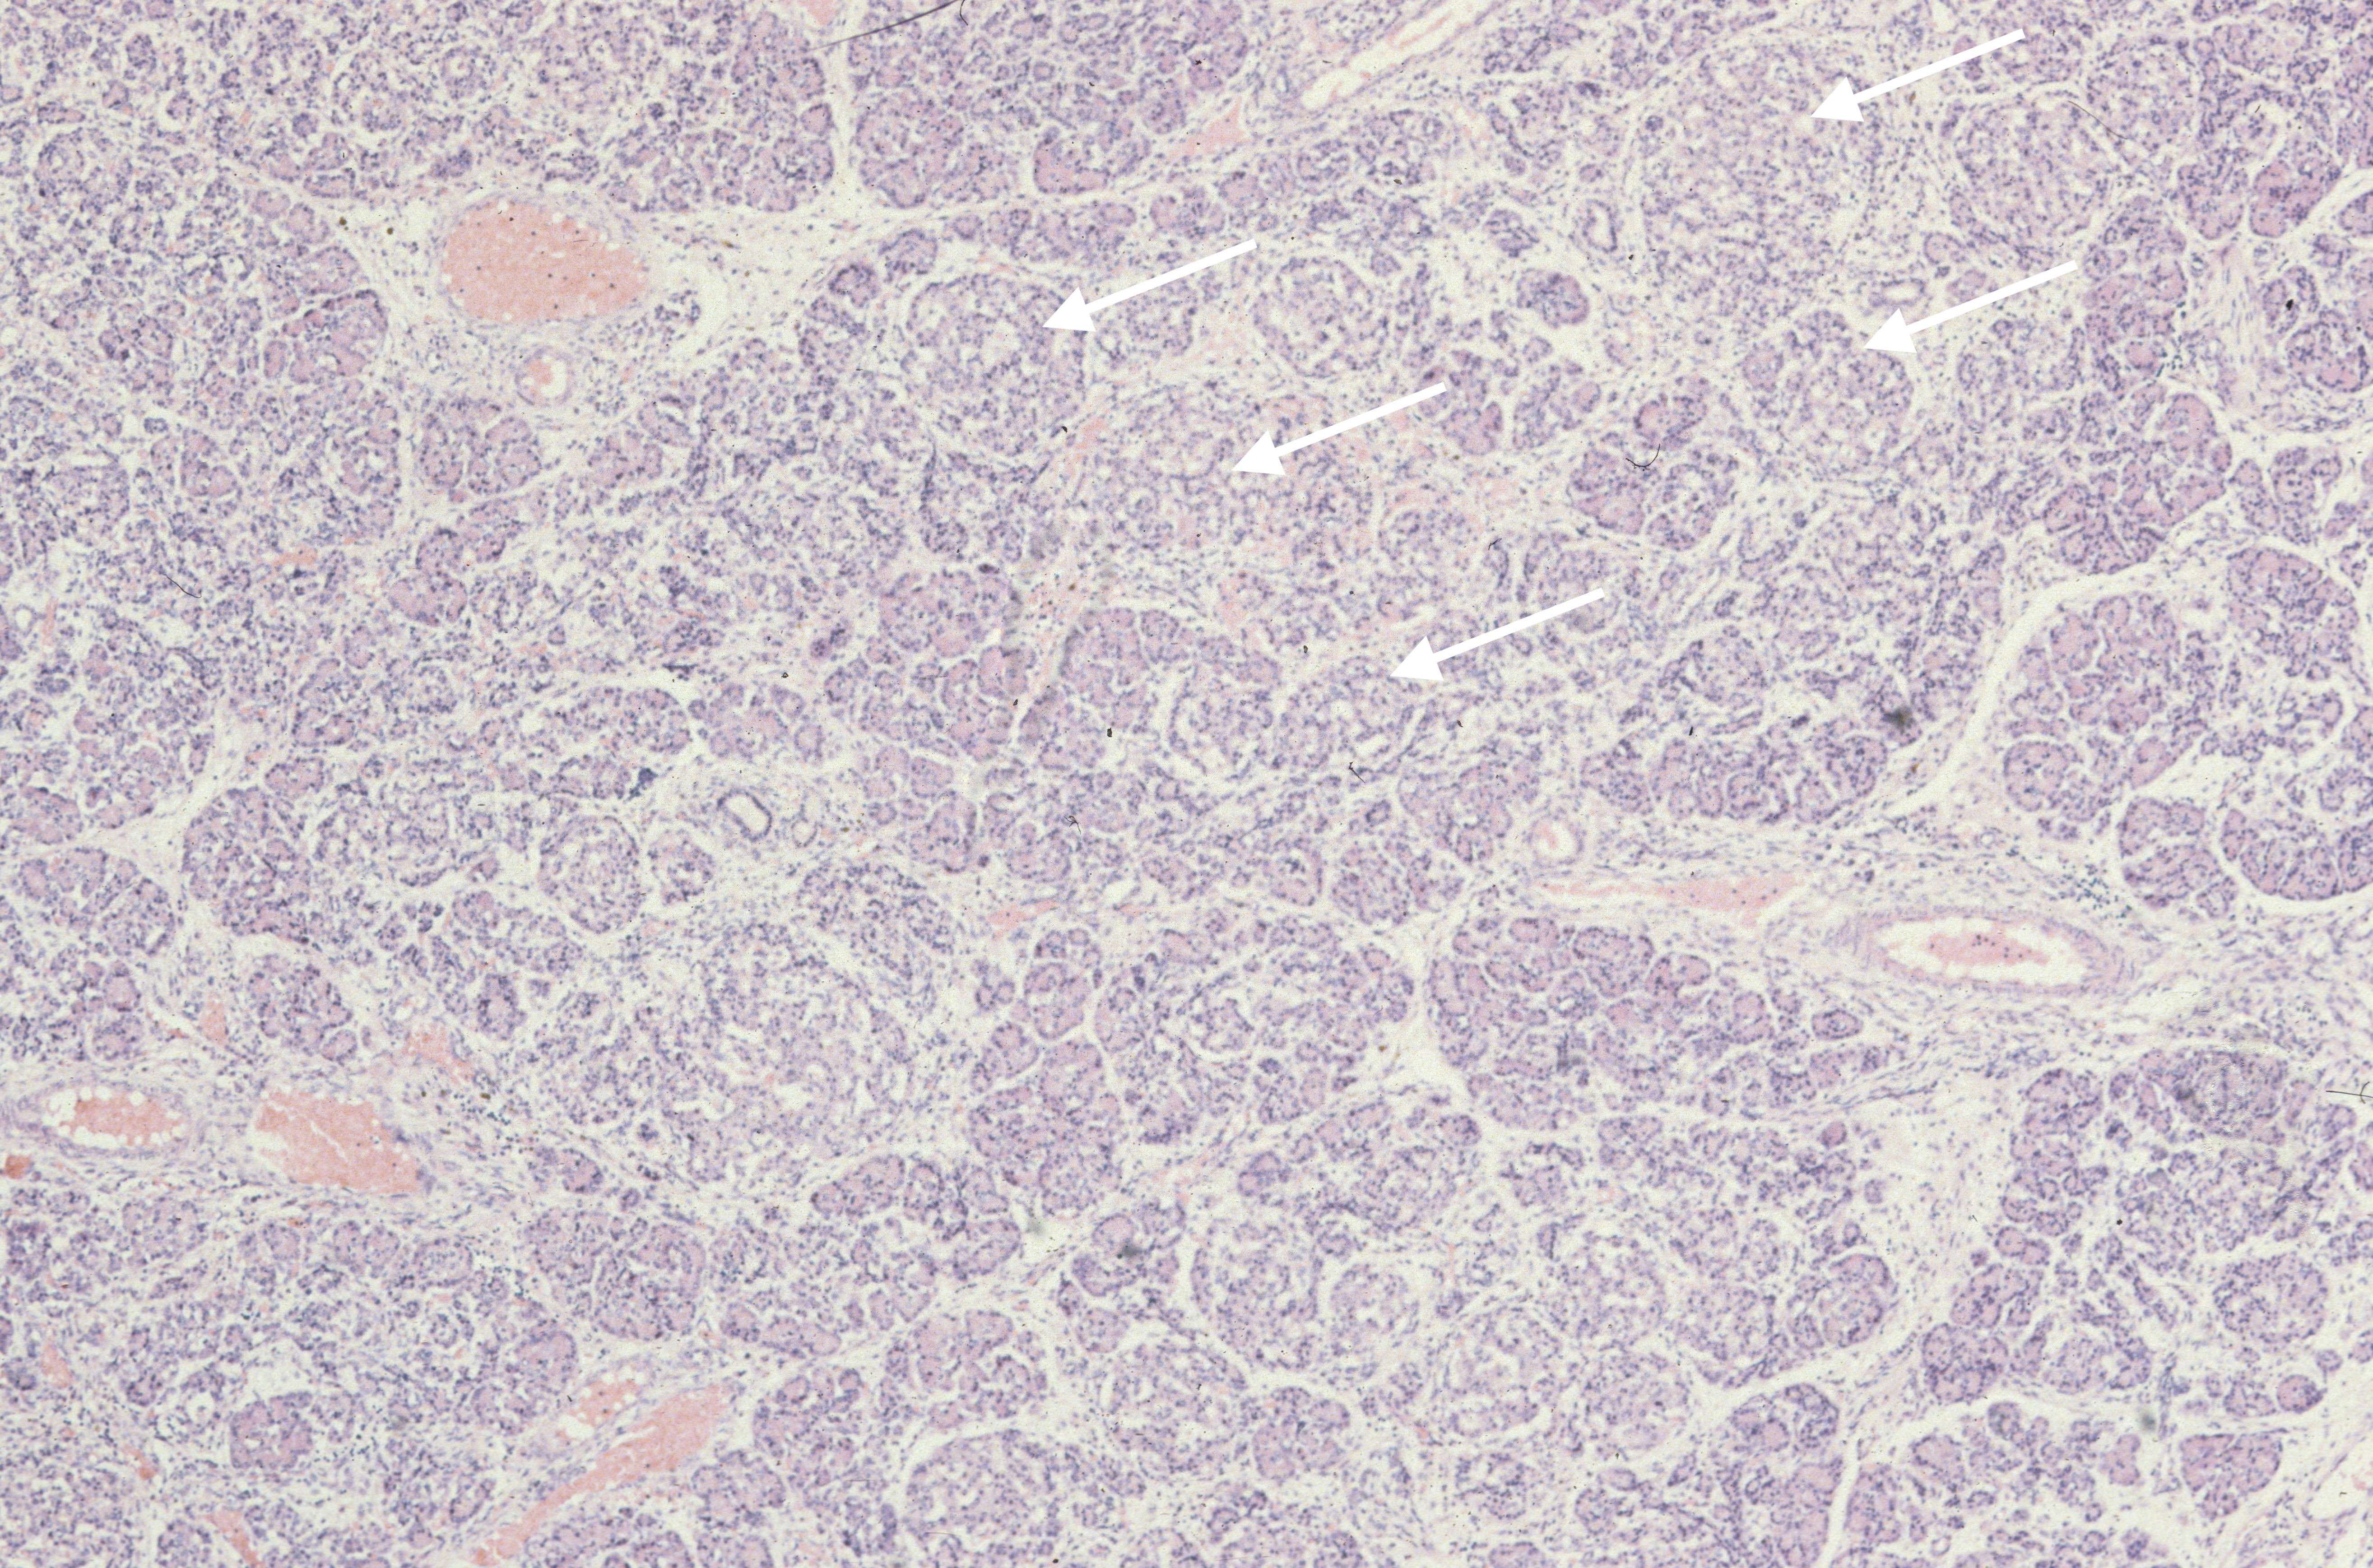

The exocrine pancreas may demonstrate malformations of the duct system such as in Ivemark syndrome of renal-hepatic-pancreatic dysplasia, Meckel Gruber syndrome, and various osteochondrodysplasias[1-3]. (Fig 2, 3) Cystic fibrosis can cause meconium ileus in utero, and may show ductal plugging in the pancreas[4]. In neonates with prolonged cachexia, often seen before total parental nutrition became available, the pancreatic ductules would be dilated with sparse secretion in the lumen.